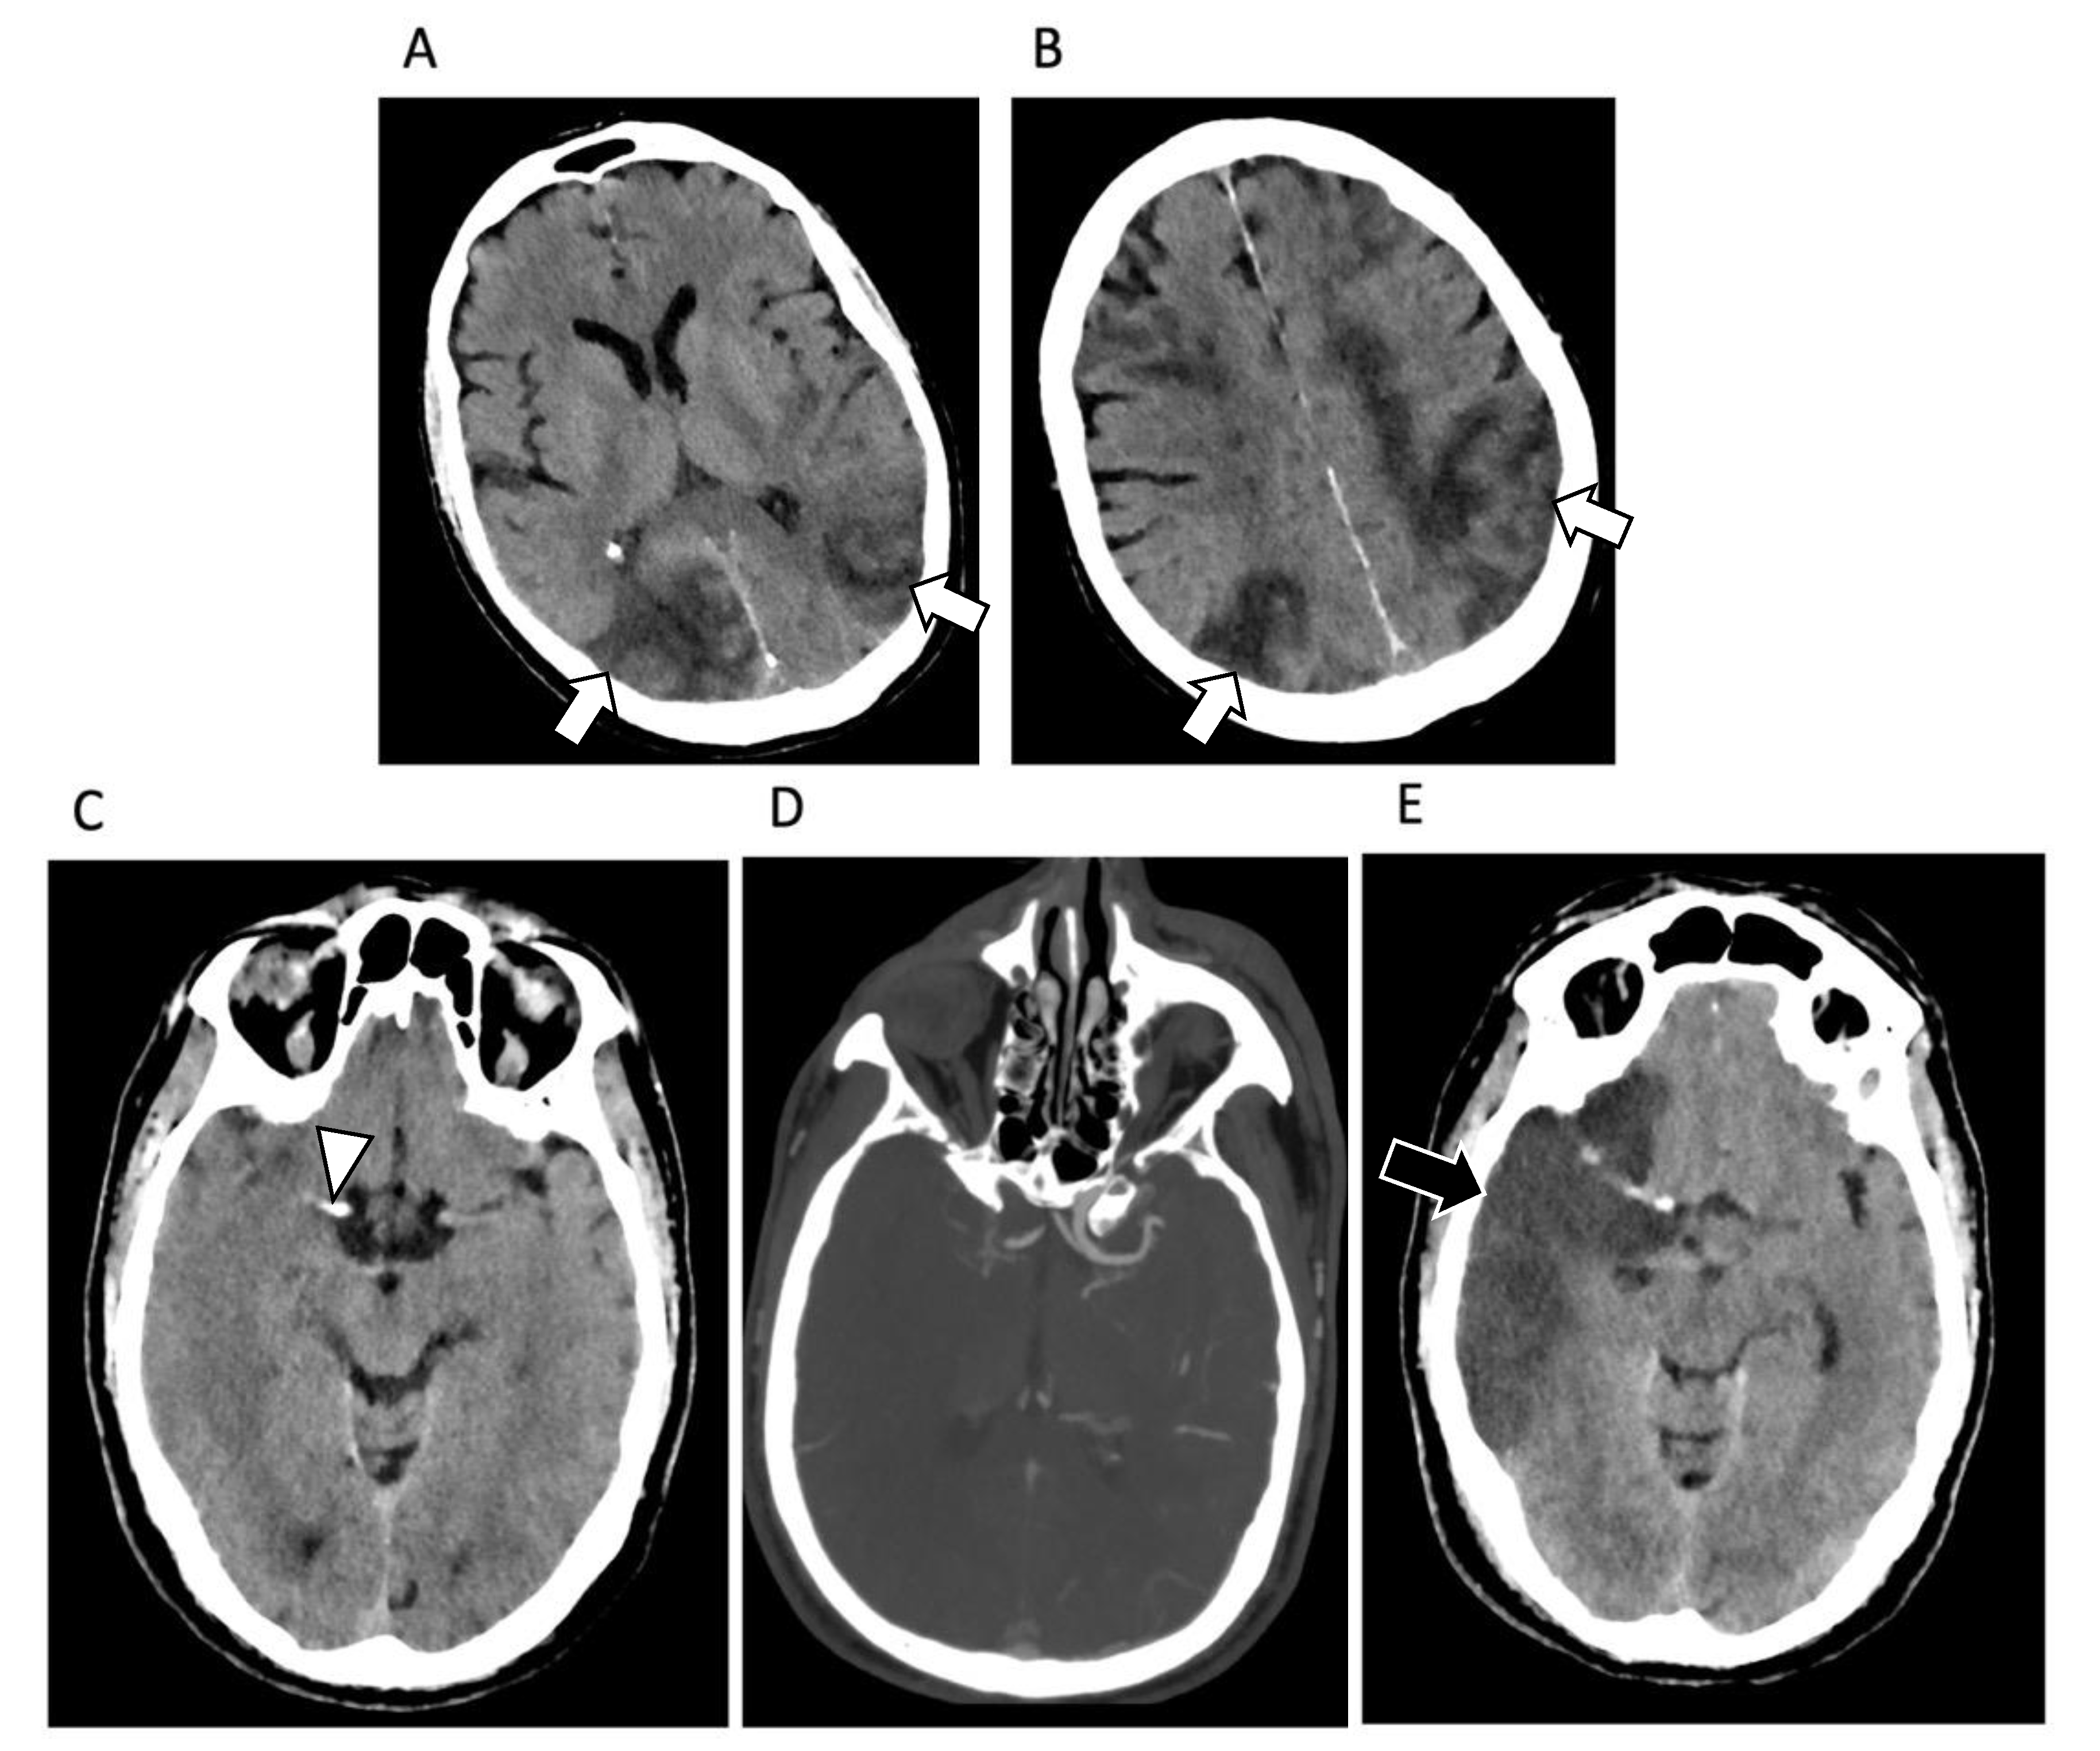

4. Central Nervous System Involvement

- Kremer, S.; Lersy, F.; De Sèze, J.; Ferré, J.-C.; Maamar, A.; Carsin-Nicol, B.; Collange, O.; Bonneville, F.; Adam, G.; Martin-Blondel, G.; et al. Brain MRI Findings in Severe COVID-19: A Retrospective Observational Study. Radiology 2020, 297, E242–E251. [Google Scholar] [CrossRef] [PubMed]

- Egbert, A.R.; Cankurtaran, S.; Karpiak, S. Brain abnormalities in COVID-19 acute/subacute phase: A rapid systematic review. Brain Behav. Immun. 2020, 89, 543–554. [Google Scholar] [CrossRef] [PubMed]

- De Stefano, P.; Nencha, U.; De Stefano, L.; Mégevand, P.; Seeck, M. Focal EEG changes indicating critical illness associated cerebral microbleeds in a Covid-19 patient. Clin. Neurophysiol. Prac. 2020, 5, 125–129. [Google Scholar] [CrossRef] [PubMed]

- Dixon, L.; McNamara, C.; Gaur, P.; Mallon, D.; Coughlan, C.; Tona, F.; Jan, W.; Wilson, M.; Jones, B. Cerebral microhaemorrhage in COVID-19: A critical illness related phenomenon? Stroke Vasc. Neurol. 2020, 5, e000652. [Google Scholar] [CrossRef] [PubMed]

- Li, Y.; Li, M.; Wang, M.; Zhou, Y.; Chang, J.; Xian, Y.; Wang, D.; Mao, L.; Jin, H.; Hu, B. Acute cerebrovascular disease following COVID-19: A single center, retrospective, observational study. Stroke Vasc. Neurol. 2020, 5, 279–284. [Google Scholar] [CrossRef] [PubMed]

- Franceschi, A.; Ahmed, O.; Giliberto, L.; Castillo, M. Hemorrhagic Posterior Reversible Encephalopathy Syndrome as a Manifestation of COVID-19 Infection. Am. J. Neuroradiol. 2020, 41, 1173–1176. [Google Scholar] [CrossRef]

- Kadono, Y.; Nakamura, Y.; Ogawa, Y.; Yamamoto, S.; Kajikawa, R.; Nakajima, Y.; Matsumoto, M.; Kishima, H. A case of COVID-19 infection presenting with a seizure following severe brain edema. Seizure 2020, 80, 53–55. [Google Scholar] [CrossRef]

- Hughes, C.; Nichols, T.; Pike, M.; Subbe, C.; Elghenzai, S. Cerebral Venous Sinus Thrombosis as a Presentation of COVID-19. Eur. J. Case Rep. Intern. Med. 2020, 7, 001691. [Google Scholar] [CrossRef]

- Gulko, E.; Oleksk, M.; Gomes, W.; Ali, S.; Mehta, H.; Overby, P.; Al-Mufti, F.; Rozenshtein, A. MRI Brain Findings in 126 Patients with COVID-19: Initial Observations from a Descriptive Literature Review. Am. J. Neuroradiol. 2020, 41, 2199–2203. [Google Scholar] [CrossRef]

- Najt, P.; Richards, H.L.; Fortune, D.G. Brain imaging in patients with COVID-19: A systematic review. Brain Behav. Immun. Health 2021, 16, 100290. [Google Scholar] [CrossRef]